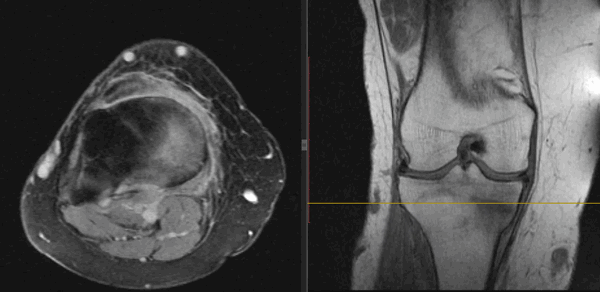

Отдельного внимания заслуживают травмы кисти, стопы. Здесь кости имеют небольшие размеры. Тени их накладываются одна на другую. Оценить состояние костной ткани гораздо точнее можно на трехмерных снимках МРТ и КТ, чем на плоскостных рентгеновских. На МРТ кроме костных нарушений будут видны также сдавление или разрыв нервов, сухожилий, отек, воспаление мышц, суставов.

Плотное вещество кости лучше исследовать на снимках КТ. На МРТ снимках кость - самая темная ткань, на КТ - наиболее яркая и светлая. Зато МРТ лучше выявляет сопутствующие переломам повреждения костного мозга, спинного мозга, нервов, сухожилий, мышц, связок.

Изучают на МРТ случаи переломов, если повреждены мягкие ткани, внутрисуставные структуры, долго не проходит симптоматика после травмы несмотря на проводимое лечение. МРТ делают, если планируется оперативное вмешательство, а также для контроля достигнутых результатов лечения. МРТ снимки позволяют создавать трехмерные изображения стопы, колена, поэтому врач может увидеть линии перелома, не заметные на обычной рентгенограмме, изучить состояние каждой косточки.